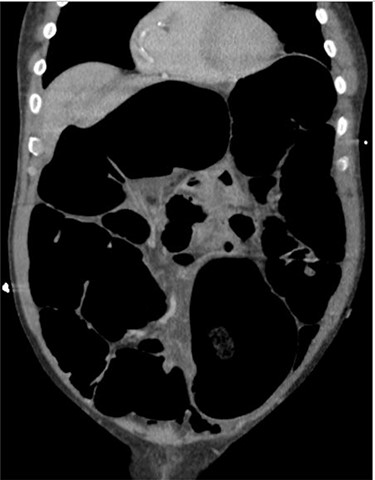

Blood tests on admission were unremarkable. Each admission, the patient’s plain abdominal films showed dilated large bowel loops consistent with sigmoid volvulus (Fig. 1). A subsequent computed tomography (CT) of the abdomen and pelvis with intravenous contrast revealed dilated large bowel and was reported as sigmoid volvulus with no evidence of perforation (Fig. 2). Caecal volvulus was not appreciated on this scan.

Case one: plain abdominal film showing dilated large bowel and the ‘coffee bean’ sign associated with sigmoid volvulus.